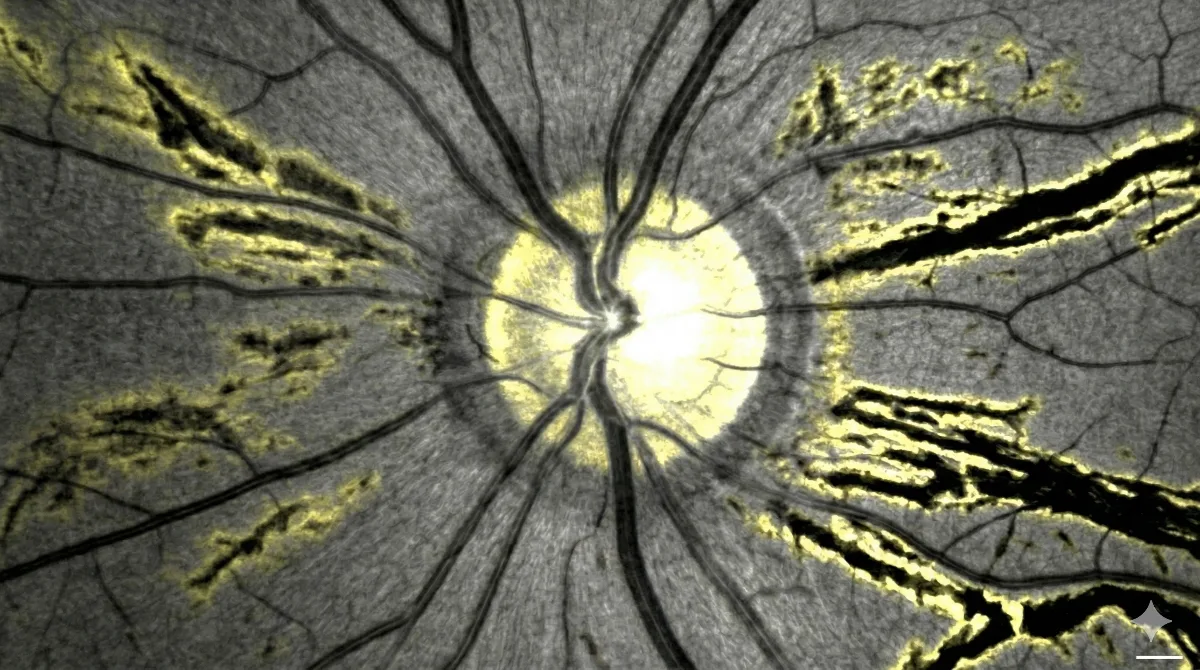

Les stries angioïdes correspondent à de petites fissures qui apparaissent dans la membrane de Bruch, une fine couche située sous la rétine. Cette membrane joue un rôle essentiel puisqu'elle sépare la rétine de la choroïde, le tissu vasculaire nourricier de l'œil. Lorsque la membrane de Bruch se calcifie progressivement, elle devient rigide et fragile. Les contraintes mécaniques naturelles exercées sur l'œil provoquent alors des ruptures qui se manifestent sous la forme de lignes brunâtres, orangées ou grisâtres, disposées en rayons autour du nerf optique.

Leur nom vient de leur ressemblance avec des vaisseaux sanguins (angioïde signifie « qui ressemble à un vaisseau »), bien qu'il ne s'agisse pas de vaisseaux mais de véritables craquelures dans cette structure profonde de l'œil. Les stries angioïdes touchent autant les hommes que les femmes et sont le plus souvent découvertes entre 30 et 50 ans, parfois de manière fortuite lors d'un examen du fond d'œil.

- Fond d'œil et rétinophotographies : les stries angioïdes apparaissent sous la forme de lignes colorées partant du nerf optique. Des signes associés comme un aspect en « peau d'orange » de la rétine ou des drusen papillaires peuvent être observés.

- Autofluorescence : cet examen non invasif rend les stries angioïdes plus visibles et permet de surveiller leur évolution ainsi que la progression d'éventuelles zones d'atrophie rétinienne.